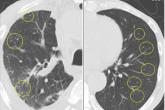

ArticleDrug reaction or metastatic lung cancer?Author:Kazuyoshi Kuwano, MD, PhDPublish date: December 1, 2017Imaging shows nodules randomly distributed throughout both lungs, a paradoxical reaction to drug therapy.Read More